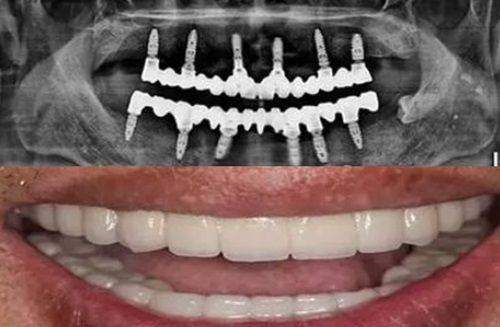

在设备方面,该门诊部引进了国内外精良的口腔诊疗设备,如数字化口腔全景机、口腔种植机等。这些设备能够精细地诊断口腔问题,为治疗提供有力的支持。同时,门诊部严格遵循消毒流程,确保每一位患者的安心。